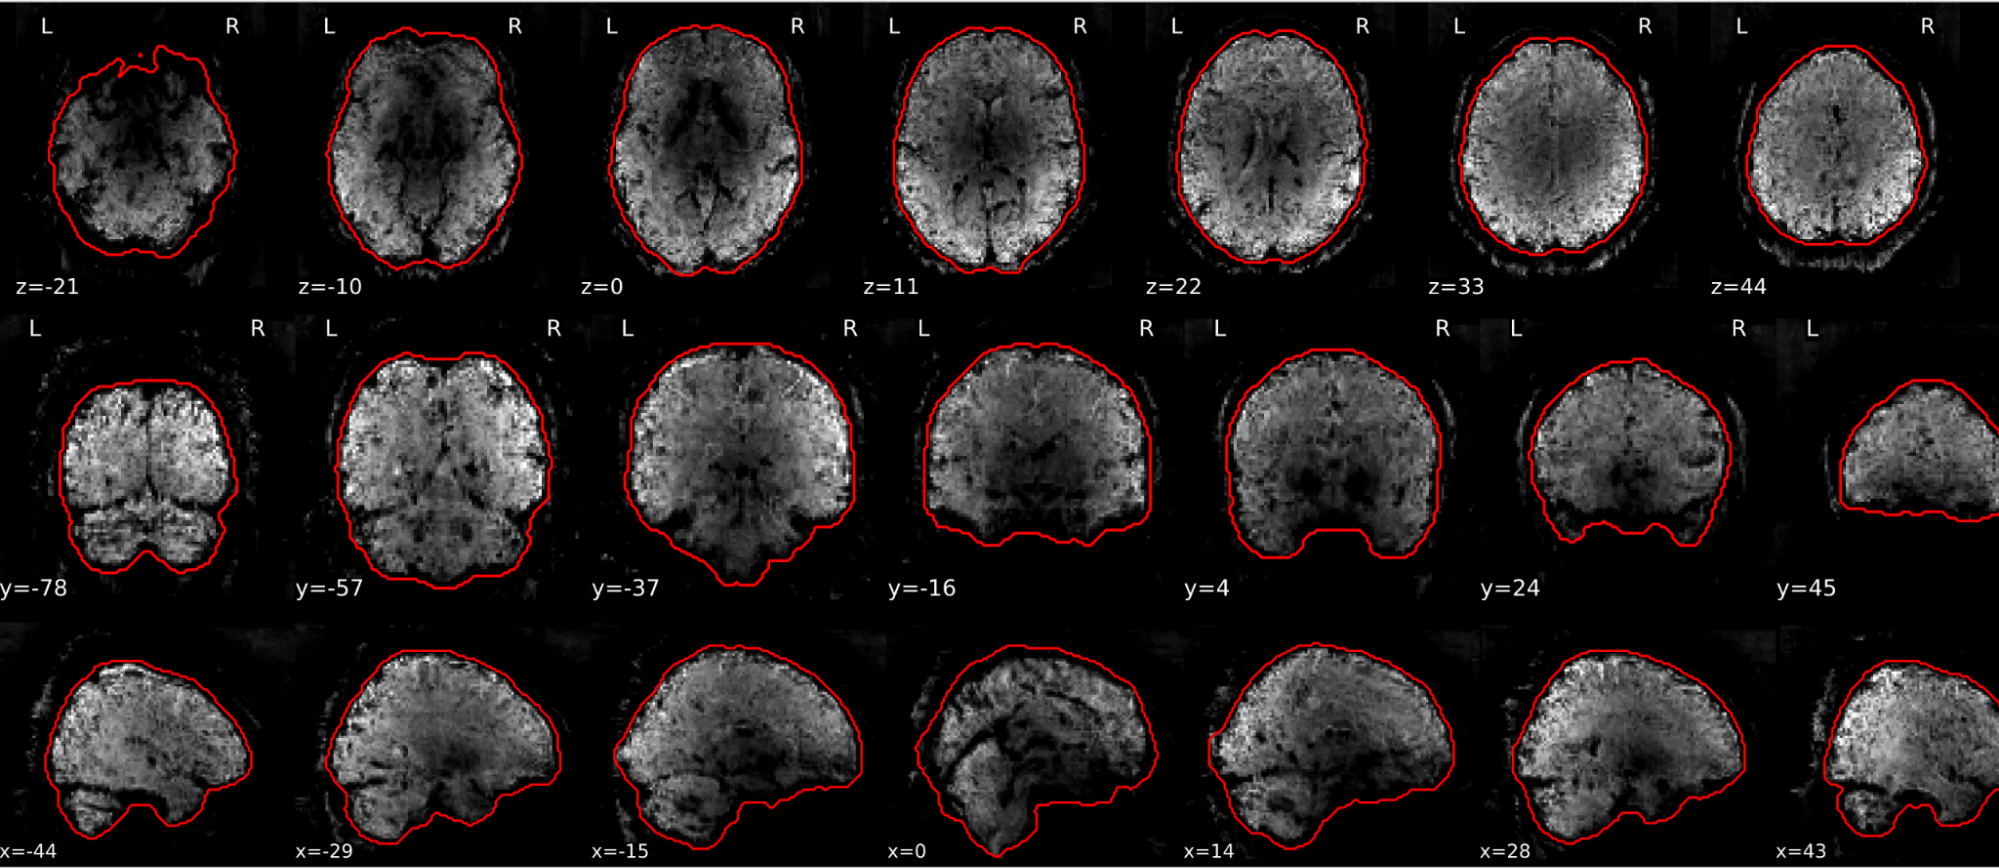

EPI tSNR

In the signal to noise ratio images of the resting state image the desired signal is compared to the amount of background noise. It is important to check all the views (sagittal, coronal, axial) because some artefacts (e.g., stripes) may be evident only in one particular view.

Example of a good subject

- Signal to noise is symmetrically distributed and there is no signal distortion

Example of a bad subject

- Asymmetry

- Potential signal distortion (might represent an artefact)

- Signal drop-out

- Stripes artefact

Clear large artefact (e.g., zebra stripes in example 1) are worth the exclusion of the subject. If you are unsure, check the other quality metrics for that subject to decide whether they should be excluded.

Summary

| good | bad |

|---|---|

| Symmetrical distribution of noise and signal | Asymmetry |

| No disruptions of the signal (no “black patches”) |

Potential signal disruptions (could be related to artefacts) |

| No stripes (sign of high motion) |

Signal drop |

| Stripe artefacts (“zebra” stripes due to motion) |